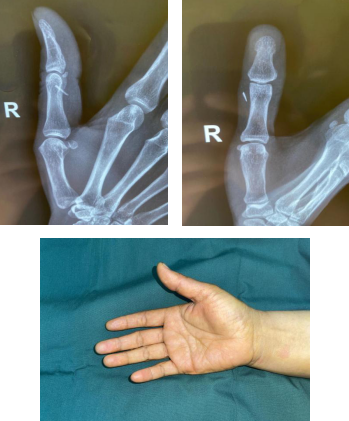

术前

6月26日上午,徐州的王大姐来到必威官方首页官网betway手外科门诊,手外二病区熊祖国医生接诊。王大姐说,2周前,她在家洗碗时不慎被碗上的瓷片划伤右拇指,本以为就破个小伤口,没有出血,所以没放在心上,仅用创可贴包扎了一下伤口。伤后10天左右,王大姐右拇指的伤口愈合了,但是她触摸伤口周围总感觉怪怪的,伤口内像是有什么东西似的。于是,王大姐立即去当地的医院就诊,拍片后发现右拇指竟有一个瓷片样异物存留在手指内。

王大姐想手术取出异物,可是辗转多家医院后均告知王大姐,瓷片较小且脆性较大,就算手术也有可能无法取出,或者取出后仍有部分断裂的瓷片留在伤口内的可能。听医生这么一说,王大姐更紧张了。亲戚听说此事,推荐王大姐到betway在线登陆手外科试试。6月26日,王大姐来到betway在线登陆手外科门诊,熊祖国医师查看王大姐的手指和片子,仔细询问病史后决定尝试手术取出异物。